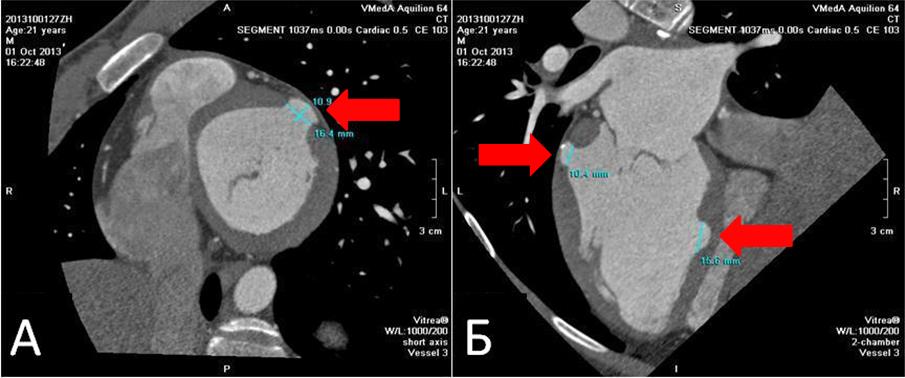

При трансторакальной эхокардиографии отмечено увеличение конечно-диастолического размера левого желудочка до 6,2 см и объёма левого предсердия до 66 мл, а также миксоматозное изменение обеих створок митрального клапана с пролапсом и регургитацией 2-й степени. Особо обращала на себя внимание выраженная неоднородность межжелудочковой перегородки с зоной локального фиброза, истончения и изменённой кинетики (акинезия, дискинезия) в средней трети (рис. 1). При компьютерной томографии сердца с контрастным усилением в 6-м и 9-м сегментах левого желудочка были визуализированы два врождённых дивертикула сердца размером 16 х 11 х 10 мм и 28 х 6 х 16 мм (рис. 2). При МРТ сердца с контрастным усилением в 6-м и 9-м сегментах левого желудочка также визуализировались врождённые дивертикулы сердца (в 6-м сегменте на всю толщину стенки левого желудочка), имевшие фиброзную стенку, с её отсроченным контрастированием. Изменения в 12-м сегменте ЛЖ были расценены как несформировавшийся дивертикул (рис. 3).